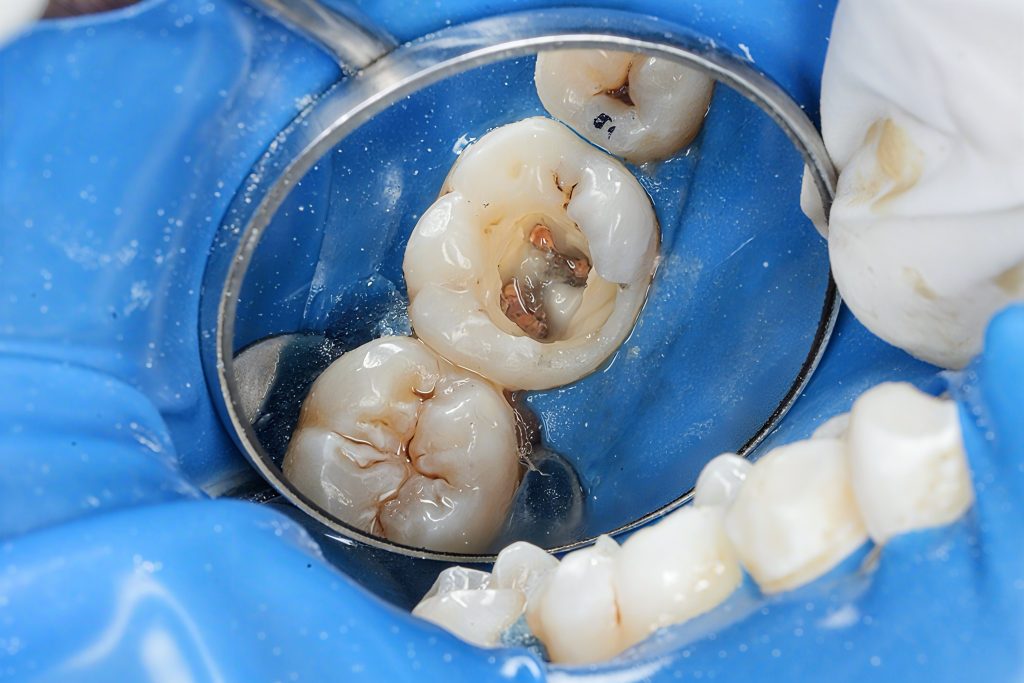

Case Assessment and Diagnosis

Clinical examination revealed a deeply carious mandibular first molar with pulpal involvement. Radiographic evaluation showed intact periapical structures and favorable root morphology. The tooth was deemed restorable with adequate remaining enamel and dentin, making it suitable for a bonded restorative approach following endodontic therapy.